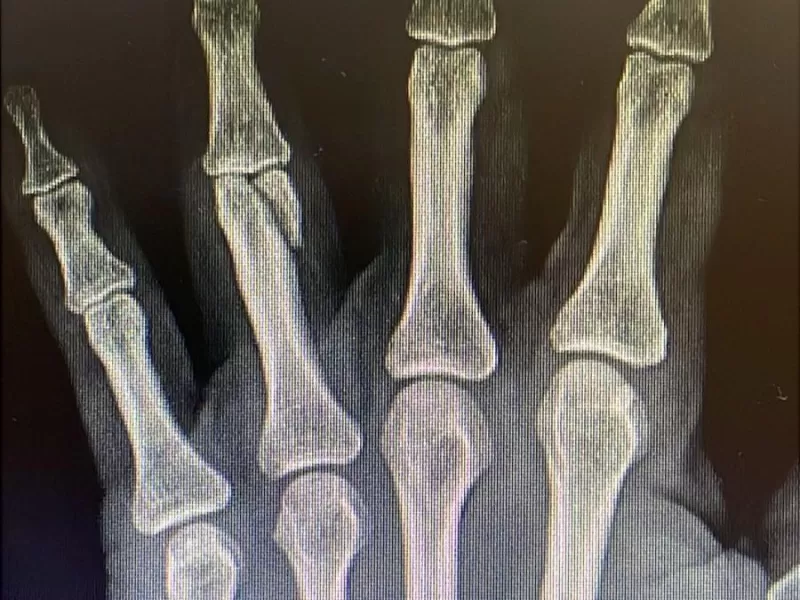

“Era algo tremendo, me pegaba sin parar. Tenía una fuerza increíble. Su intención era matarme”, relató la víctima. Carolina cayó al suelo, completamente ensangrentada, intentando defenderse como podía. Al frenar varios golpes con las manos sufrió la fractura de un dedo, lesión que requerirá una operación.

La mujer fue trasladada a la Comisaría Primera de La Plata, la denuncia quedó caratulada como lesiones graves, principalmente por la fractura sufrida por la víctima. El fiscal de la causa es Juan Condomi Alcorta. Según la primera evaluación médico-policial, estaría ubicada en tiempo y espacio y sería consciente de sus actos. Y ahí aparece el mayor temor de todos: que quede libre y vuelva al barrio.